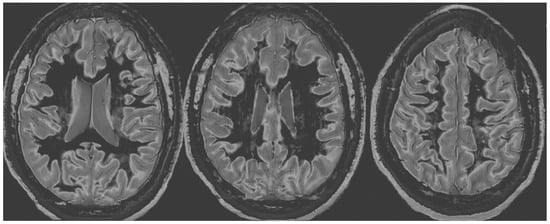

Figure 6 and Figure 7 show T2-FLAIR images (upper rows) with positionally matched dSIR images (lower rows). No abnormalities are seen in the white matter on the T2-FLAIR images, but very extensive high signal abnormalities are seen in the white matter of the corresponding dSIR images. There is relative sparing of the anterior central corpus callosum and, to a lesser extent, the posterior central corpus callosum. There is also some sparing of the peripheral white matter in the cerebral hemispheres.

Overall, the MRI findings in Case 2 are very similar to those in Case 1, as shown in Figure 4 and Figure 5. They have been described as a whiteout sign. This often involves 80% or more of the white matter in the cerebral and cerebellar hemispheres having an abnormal high signal appearance.

Figure 6. Case 2 was examined two years after his asphyxial episode. Comparison of positionally matched T2-FLAIR images (upper row) and narrow mD dSIR images (lower row). No abnormality is seen on the T2-FLAIR images, but there are extensive areas of high signals in the white matter of the brain. The anterior and posterior central corpus callosum and parts of the frontal lobes have a lower, more normal signal (darker appearance). Horizontal CSF flow artefacts are seen in the dSIR image in the middle lower row.